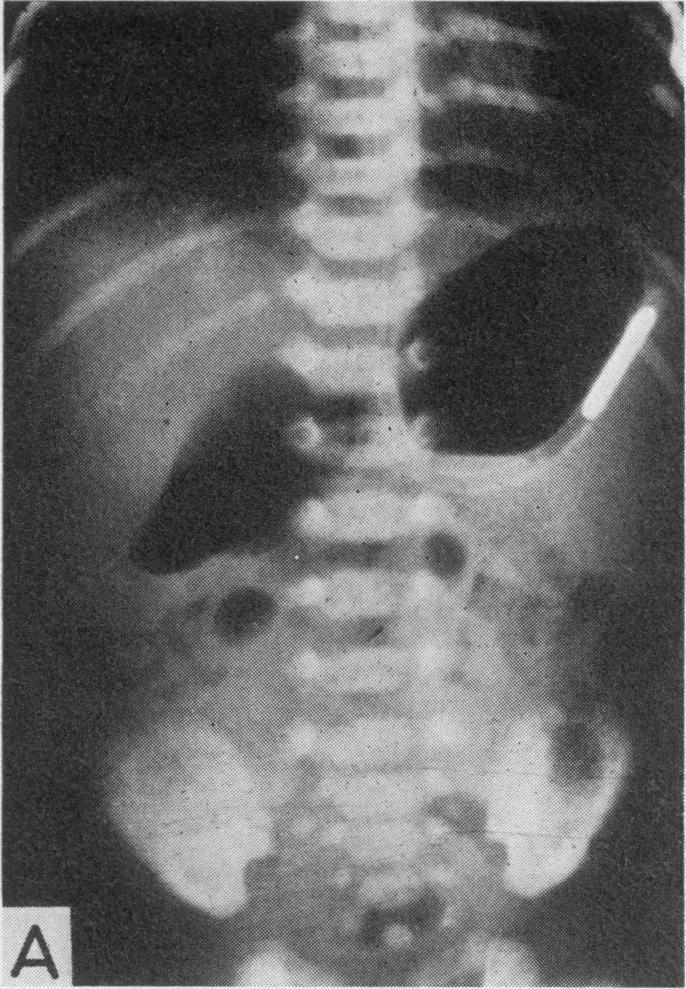

Pitfalls in the diagnosis of intestinal obstruction in the newborn.

Proc R Soc Med. 1971 Apr;64(4):374-7. doi: 10.1177/003591577106400417.